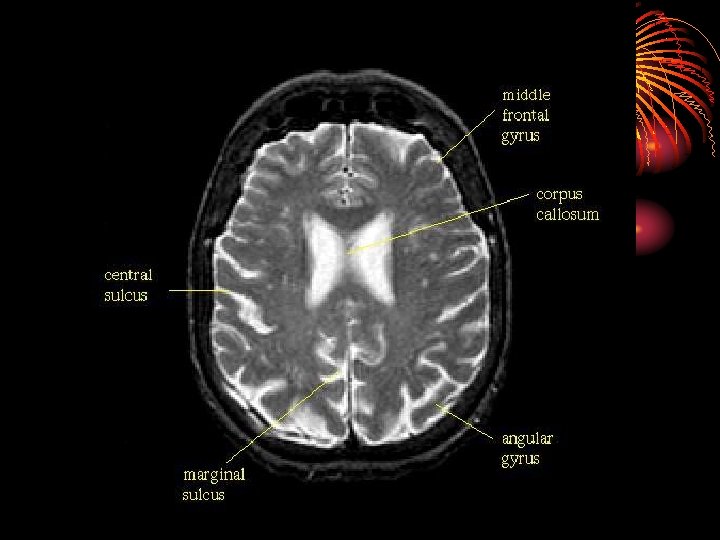

• Magnetic Resonance Imaging (MRI) • A technique that uses magnetic fields and radio waves to produce computergenerated images that allow us to see structures within the

• The CEREBRAL CORTEX is the intricate, wrinkled covering of the brain (FISSURES) (actually a bump is a gyrus and a groove is a sulcus – but that’s a bit too much info…) • In addition to interneurons, it contains GLIAL CELLS, which guide neural connections, provide nutrients to myelin, and mop up neurotransmitters

• The two hemispheres of the brain are connected by the CORPUS CALLOSUM

• The Cerebral Cortex is split into four LOBES, with half of each one on the left, and half of each one on the right: • The FRONTAL LOBE PARIETAL LOBE OCCIPITAL LOBE TEMPORAL LOBE

• The Frontal Lobes are the portions of the cortex lying just behind the forehead • Mostly involved in abstract thought, speaking, muscle movements, making plans, and judgments

• Along the top of both front lobes runs the motor cortex

• The Parietal Lobes are the portion of the cortex lying at the top of the head includes the sensory (or somato-sensory) cortex

• The Temporal Lobes are the portions of the cerebral cortex roughly located above the ears • audio processing • comprehension, naming, verbal memory and other language functions.

• The Occipital Lobes are located at the back of the head • The occipital lobe is responsible for processing visual information.